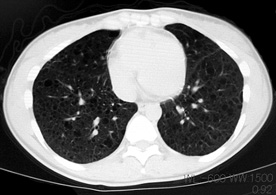

LAM患者さんに認められた両側肺気腫(右図:胸部CT)

firstCT.jpg

初診時CT(左)から2年後のCTでは肺の嚢胞化が著明となっている。